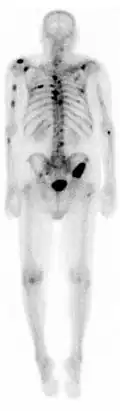

Exemplo de gamagrafia de corpo inteiro.

Cintigrafia óssea ou gamagrafia óssea é uma técnica de diagnóstico por imagem de medicina nuclear usada para diagnosticar várias condições ósseas, incluindo cancro (primário ou metástase) no osso, osteíte(inflamação do osso), fraturas ou fissuras ósseas (que podem não ser visíveis em imagens de raios X tradicionais) e infecção óssea (como artrite séptica).[1]

A cintigrafia fornece imagens funcionais, permitindo a visualização do metabolismo ósseo ou da remodelação óssea, que técnicas de imagem como tomografia simples e raio X não conseguem. O PET Scan (tomografia por emissão de positrões) também permite imagens funcionais do metabolismo, mas é consideravelmente mais caro.[2]